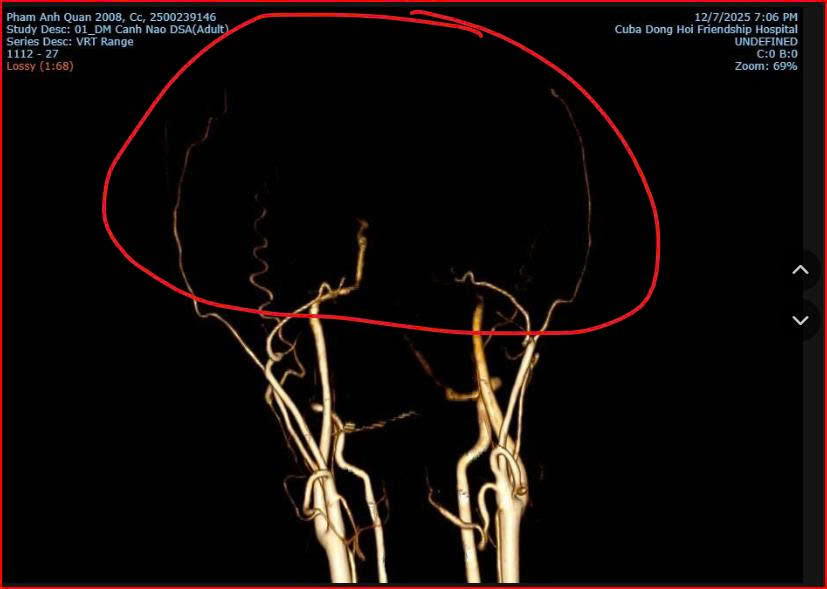

Trao đổi với phóng viên Báo Người Lao Động, bác sĩ Nguyễn Đức Hùng, Trưởng Khoa Chẩn đoán hình ảnh - Bệnh viện Hữu nghị Việt Nam - Cuba Đồng Hới, đã đưa ra nhận định chuyên môn ban đầu dựa trên các dấu hiệu lâm sàng và hình ảnh chẩn đoán.

"Không phải tử vong do bị đánh mà do bệnh lý có sẵn"Theo bác sĩ Hùng, sau khi xem kỹ video về các biểu hiện của Q. trước khi ngã và kết quả hình ảnh mà bệnh nhân vào cấp cứu tại bệnh viện này cho thấy nhiều khả năng em Q. tử vong liên quan đến bệnh lý phình mạch máu não bẩm sinh - một dị dạng mạch não có thể vỡ bất cứ lúc nào, nhất là khi gắng sức.

"Phình mạch não giống như "cái săm xe đạp" phồng lên bên trong mạch máu. Nó có thể vỡ bất kỳ lúc nào nếu áp lực tăng đột ngột. Trong lúc xô xát, nhịp tim và huyết áp của cháu Q. tăng mạnh, gây tăng áp lực nội sọ và khiến túi phình vỡ dẫn đến xuất huyết não" - bác sĩ Hùng giải thích.

Co thắt mạch máu não do xuất huyết não và vỡ phình mạch

Bác sĩ Hùng cho biết phình mạch não là bệnh lý sâu, chỉ được phát hiện khi chụp các kỹ thuật chuyên sâu như CT mạch não hoặc MRI mạch não. Người mắc dị dạng này thường không có triệu chứng rõ ràng. Dấu hiệu "ngã rơi tự do" cho thấy não đã xuất huyết trước khi cơ thể tiếp đất.

Hình ảnh CT/MRI: Xuất huyết dưới nhện do vỡ phình mạch máu não của bệnh nhân Phạm Anh Q. thời điểm tại Bệnh viện Hữu nghị Việt Nam - Cuba Đồng Hới

Bác sĩ Hùng khẳng định theo hình ảnh chuyên môn y khoa từ chẩn đoán thì không có dấu hiệu nào cho thấy nạn nhân bị đánh với lực đủ mạnh để gây gãy cổ hoặc chấn thương sọ não do tác động ngoại lực.

Phân tích từ hình ảnh chẩn đoán, bác sĩ Hùng cho biết không phát hiện tổn thương xương cột sống cổ, không có tổn thương vòm sọ, không có tổn thương não do lực tác động bên ngoài. Đồng thời chỉ ghi nhận xuất huyết não lan tỏa và phù não, điển hình của vỡ phình mạch não.